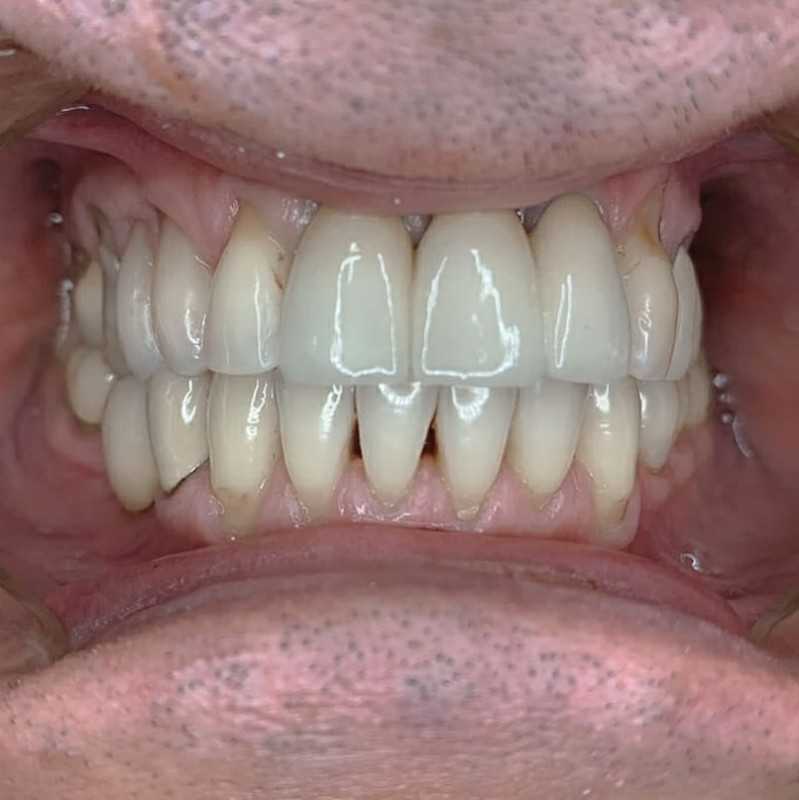

Жалобы: на отсутствие зубов, неудовлетворительную эстетику зубных рядов, невозможность жевать, подвижность зубов. Что сделано: удаление зубов на в/ч и н/ч, установка имплантатов Bredent Sky (верхняя челюсть 6 импл, нижняя 4 импл) и одномоментное протезирование акриловыми протезами с опорой на имплантаты по протоколу Fast & Fixed (зубы за один день). Через 10 месяцев проведена работа по замене протезов на постоянные металлокерамические. Что получил пациент: красивую улыбку, возможность нормально питаться с первого дня после операции.